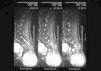

Fig. 3.—Detalle histológico del tumor. (Hematoxilina-eosina, ×10.)

En el examen histológico se observó una neoplasia maligna constituida por células fusiformes de aspecto neuroide dispuestas en haces entrelazados y ondulados ocupando la dermis. Existían amplias áreas de necrosis, hemorragias, alto índice mitótico con mitosis atípicas y degeneración mixoide. La neoplasia, con bordes parcialmente lobulados, infiltraba hasta el tejido celular subcutáneo, sin que pudiera precisarse el límite de la lesión. La piel perianal no estaba comprometida.

Con tinciones para reticulina se observaron fibrillas rodeando grupos celulares y perivasculares.